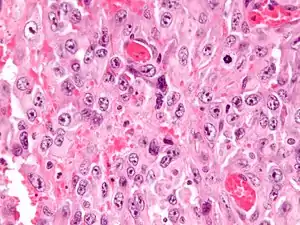

| Micrograph of an epithelioid sarcoma. H&E stain. | |

Histologically, epithelioid sarcoma forms nodules with central necrosis surrounded by bland, polygonal cells with eosinophilic cytoplasm and peripheral spindling.[3] Epithelioid sarcomas typically express vimentin, cytokeratins, epithelial membrane antigen, and CD34, whereas they are usually negative for S100, desmin, and FLI1 (FLI-1).[3] They typically stain positive for CA125.[4]